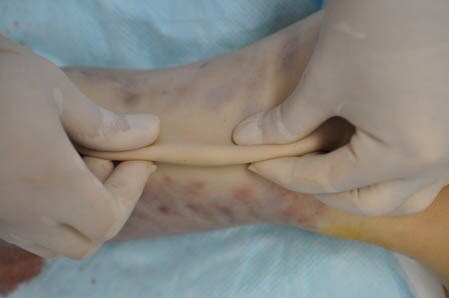

上の画像の部分をつまんでみましょう。

↓ ↓ ↓